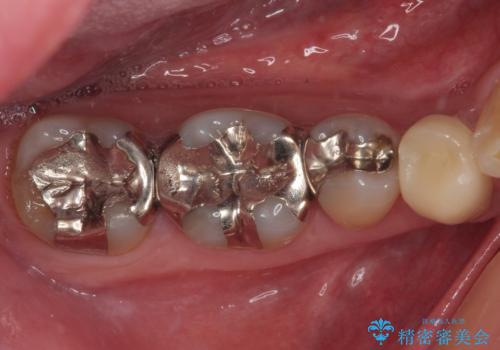

銀歯の下の虫歯を治したい オールセラミッククラウン・セラミックインレー修復

銀歯をセラミックにしたい オールセラミッククラウン

銀歯を外したい オールセラミッククラウン

右下の銀歯が外れた オールセラミッククラウン